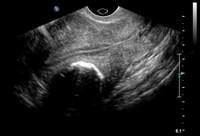

Solitary intramural fibroid as shown by transvaginal pelvic ultrasound (TVUS) demonstrating posterior intramural mass lying between a normal-appearing trilaminar endometrial stripe and posterior uterine serosa

From the personal collection of Dr M.F. Mitwally and Dr R.J. Fischer; used with permission